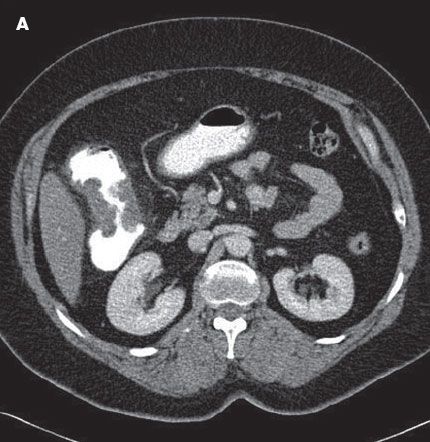

The patient had tenderness in the right upper quadrant, without signs of peritonism. A CT scan with contrast of the abdomen and pelvis demonstrated an apple core lesion (A). Colonoscopy revealed an ulcerated mass in the ascending colon, which strongly suggested malignancy (B). However, a biopsy specimen of the lesion showed only inflammatory changes with areas of ulceration (C).

The radiological hallmarks of the classic colonic apple core lesion are short, sharply defined regions of annular colonic narrowing with overhanging margins; ulcerated mucosa; and eccentric, irregular lumen. An apple core lesion can have a number of causes, the most serious being malignant neoplasm. The differential diagnosis for colitis is wide and includes inflammatory bowel disease (Crohn disease and ulcerative colitis); diverticulitis; and infective, microscopic, and drug-related colitis.